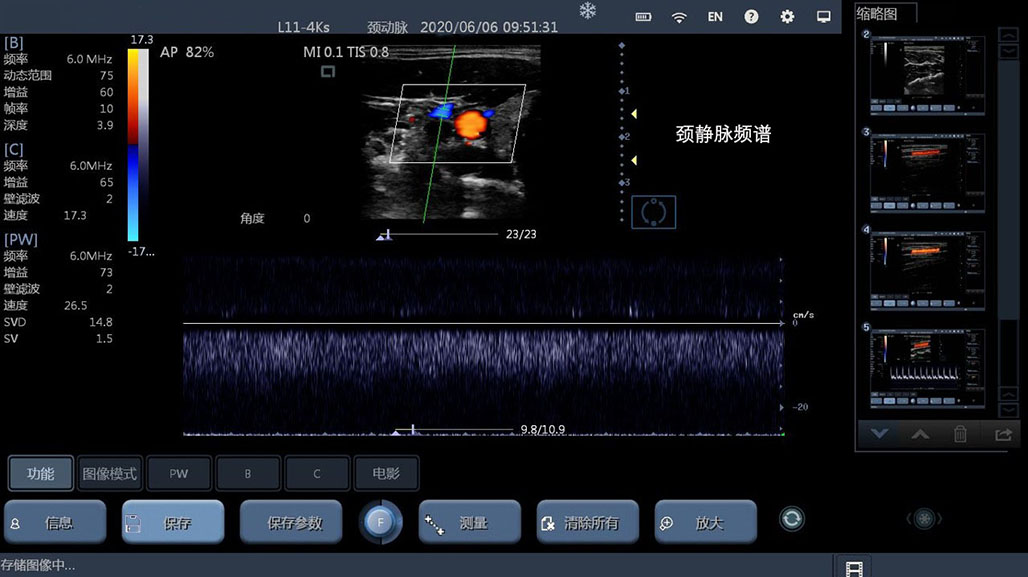

• 线阵

甲状腺

血管

神经

肌骨等